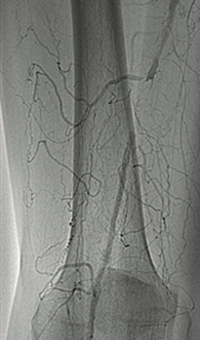

Venous thrombosis extending from popliteal to external iliac vein

Extensive DVT of the right common femoral and external iliac was treated with the 8 F AngioJet™ ZelanteDVT™ catheter.

Patient history

73 year old with 1-week old right leg swelling and pain.  Started on anticoagulation and discharged.

Consult confirmed extensive DVT from popliteal extending into external iliac vein.

Procedural steps

• Power Pulse ( tPA 10 mg in 50 cc)

• Patient put on 2-hour lytic catheter drip in holding area

• Thrombectomy performed with 8F ZelanteDVT catheter

• Directional ability of ZelanteDVT allowed targeting of residual thrombus in Popliteal and Superficial Femoral Vein Post Venography shows complete resolution of thrombus

xray of occlusive thrombus extending into the iliac vein.

Occlusive thrombus extending into the iliac vein

xray of femoral vein pre-treatment.

Femoral vein pre-treatment